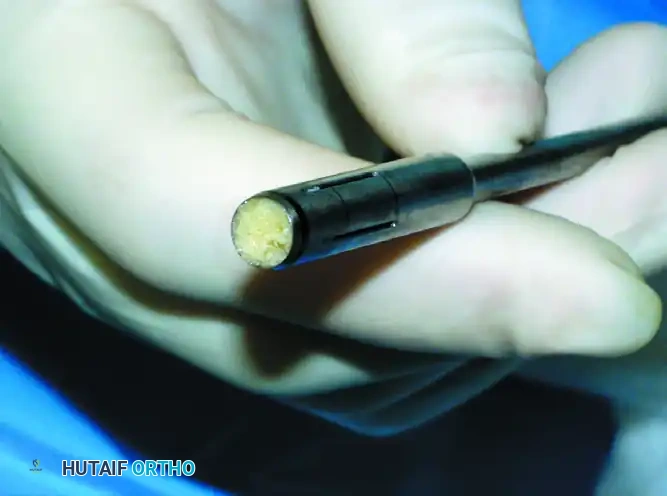

Step 2: Donor Graft Harvesting

Attention is turned to the ipsilateral knee. The graft is harvested either arthroscopically or through a small mini-arthrotomy.

* Donor Sites: The periphery of the medial femoral condyle, the lateral femoral condyle (proximal to the sulcus terminalis), or the lateral trochlea (specifically for talar shoulder lesions to match the contour).

Use the specially designed donor harvester corresponding to the exact diameter of the recipient hole (5 to 11 mm). Drive the harvester perpendicularly into the donor site to a depth of 10 to 12 mm.

Surgical Pearl: The donor graft should be harvested 1 to 2 mm deeper than the recipient hole (e.g., 12 mm donor depth for a 10 mm recipient hole). This ensures that the subchondral bone of the graft bottoms out in the recipient socket, providing structural stability while allowing the cartilage cap to sit flush.

Extract the donor plug. Inspect the cylindrical graft within the harvester to ensure the cartilage cap is intact and the bone cylinder is structurally sound.